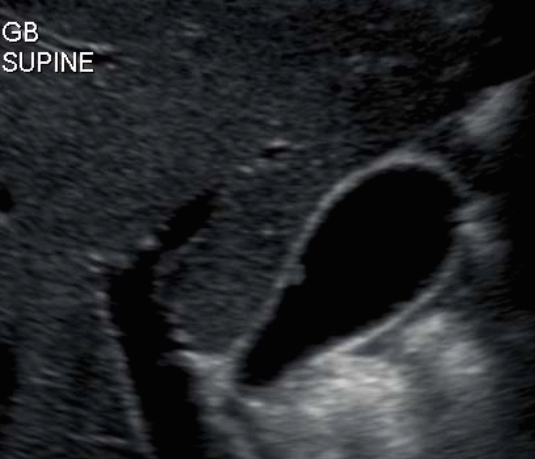

담낭 용종 ( GB polyp ) 담낭 안쪽 벽에서 담낭 안으로 돌출된 다양한 형태의 점막이 두꺼워진 것이다. 용종 자체로는 큰 문제를 일으키지 않으나, 용종의 크기가 커지면 암으로 변할 가능성이 높다. 용종의 크기가 직경 10mm 이상인경우 악성일 가능성이 높다.

발생빈도는 성인의 약 3~7% 정도이고 남성보다는 여성에서 2배 정도로 많으며 40대에서 많이 발생한다. 증상이 없으며 우연히 발견되나 드물게 명치끝이나 우상복부에 통증을 호소하는 경우도 있다.

1cm 이상의 담낭 용종은 수술로 담낭 전체를 제거하는 것을 원칙으로 하고, 1cm 미만인 경우는 주기적인 추적관찰을 한다. 용종의 크기가 1cm 미만이라 하더라도 담석이 동반되어 있거나, 증상( 복통, 담낭염등)이 있는 경우는 제거하는 것이 좋다.